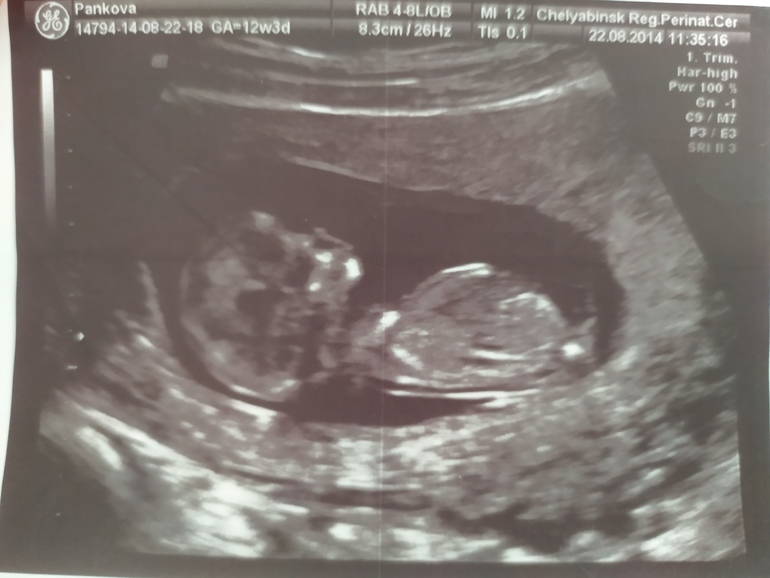

14недель.узи

УЗИ, КТГ, доплерХодила на УЗИ что бы померить шм.сейчас у меня 14 недель. 38м все хорошо. А потом врач спросили, кого я хочу?ну так как у меня есть 2 девочки, Я говорю мальчика, и симптомы прям все как с сыном, так вот мальчиком сказали не пахнет😒😒😒а я с 1 дня прям жду мальчика, даже расстроилась слегка😔потом думаю ладно, главное что бы здоровая. Дали фото на память, и на экране

Половой бугорок как у девочки, у мальчика торчит вверх. Вот мой сын

Судя по наклону бугорка действительно не пахнет мальчиком) И правда главное здоровье малыша, да и 3 принцессы по моему просто чудесно. :)

Писюн как у девочки. Но у моей такой был в 12+1 недель. Более точно узнаёте на 2м скрининге.